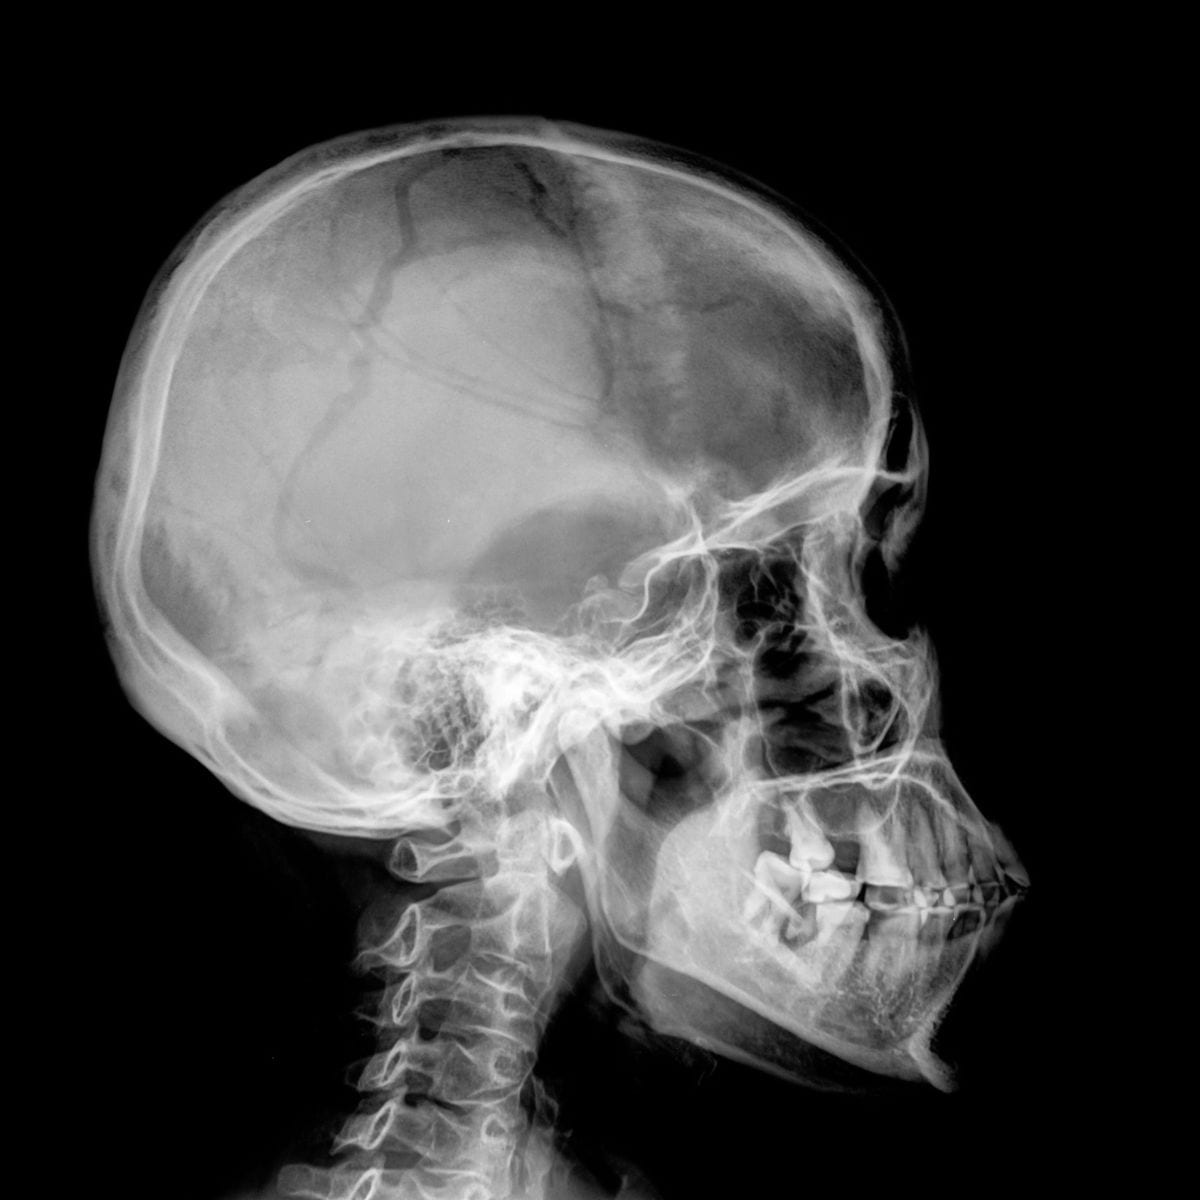

Radiografie: In molti casi, saranno eseguite radiografie dentali per ottenere una visione più dettagliata della salute dei vostri denti e delle strutture sottostanti.